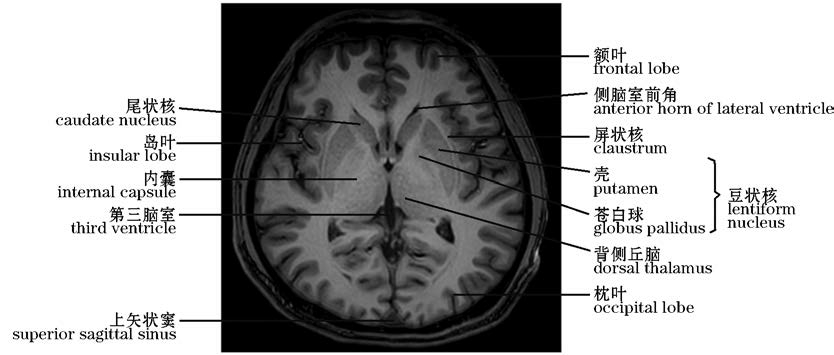

图10-37 经基底核区的横断层MRI(T 1 WI)

The MRI Cross section of the basal ganglia(T1 WI)